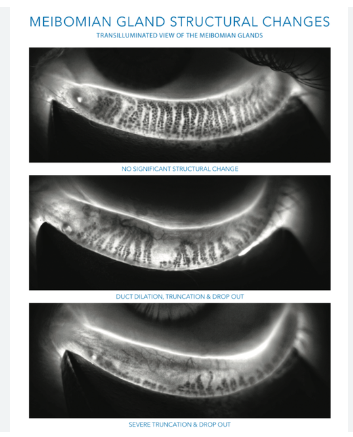

IPL therapy for dry eyes uses pulses of light to target the inflammation and clogged oil glands (meibomian glands) that contribute to dry eye symptoms. It’s a non-invasive treatment, and sessions are typically quick – around 15-20 minutes.

IPL is typically recommended for patients with evaporative dry eye, often caused by meibomian gland dysfunction (MGD) – a condition where the oil glands along the eyelid margin become clogged or inflamed. This leads to an unstable tear film and symptoms like burning, watering, or the feeling of “something in your eye.”